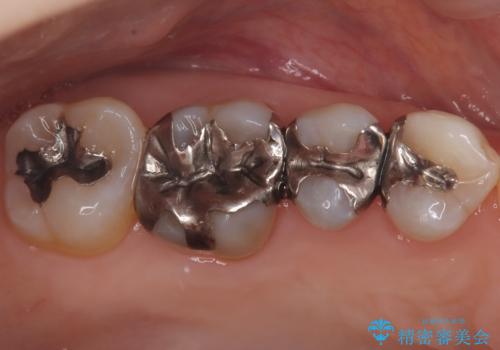

- 左上奥歯に入っている金属の詰め物(メタルインレー)の見た目を改善したいという主訴でご来院されました。お口の中の金属をなくしたいという患者様のご希望を踏まえ、天然歯に近い色と質感を持つセラミックインレーに交換する治療計画を立案。これにより、見た目の改善だけでなく、金属アレルギーのリスクを排除したメタルフリーの環境を実現することを目指しました。

治療では、まず古い金属のインレーを慎重に取り外しました。金属の下に隠れていた虫歯の再発がないかを確認し、歯を丁寧に形成。その後、精密な型取りから患者様の歯の色に合わせたオーダーメイドのセラミックインレーを作製しました。セラミックは、自然な光の透過性を持つため、周囲の歯と区別がつかないほどの美しい仕上がりとなります。適合性の高いセラミックインレーを装着することで、再発のリスクを抑えつつ、長年のコンプレックスだった銀歯がなくなり、笑顔でも気にならない自然な奥歯を取り戻していただけました。